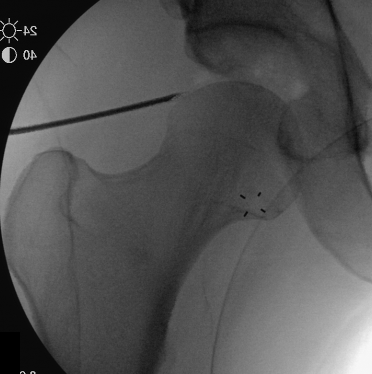

PALA

Insertion of PALA under image intensifier

PALA - Proximal anterolateral viewing portal

- entry point anterolateral aspect greater trochanter

- image intensifer

- insert just above head to avoid translabral penetration (between acetabulum and labrum)

- typically 20 degrees posterior depending on patient size

- guide wire / dilators / cannula